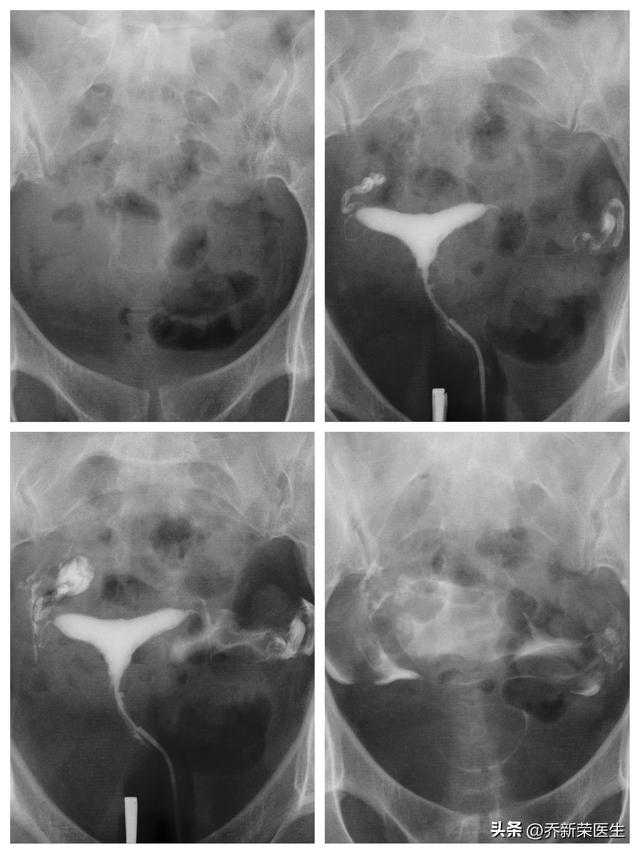

结果是这样的:左侧输卵管通而不畅,右侧输卵管通而极不畅

对于今天的造影结果,她还是表情舒展了些,自认为不像之前那么糟糕了,我还没开口下一步治疗方案,她说刚才外面就诊的病友和她情况差不多直接做疏通治疗了,你也给我做吧。